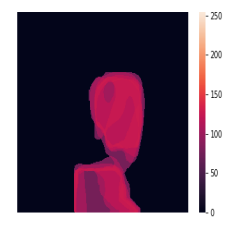

A few sample images and the corresponding masks of the polyp dataset in HyperKvasir are shown in Fig 2. The polyp images are RGB images. The masks of the polyp images are single-channel images with white () for true pixels, which represent polyp regions, and black () for false pixels, which represent clean colon or background regions. In this dataset, there are different sizes of polyps. The distribution of polyp sizes as a percentage of the full image size is presented in the histogram plot in Fig 3, and we can observe that there are more relatively small polyps compared to larger polyps. Additionally, a subset of this dataset was used to prove that the performance of segmentation models trained with small datasets can be improved using our SinGAN-Seg pipeline, and the whole dataset was used to show the effect of using SinGAN-Seg generated synthetic images instead of a large dataset which has enough data to train segmentation models. In this regard, this dataset was used for two purposes:

In total, we have generated synthetic polyp images and the corresponding masks. SinGAN-Seg generates random samples with high variations when the input scale is . This variation can be easily recognized using the standard deviation (SD) and the mean mask images presented in Fig 5. The mean and SD images were calculated by stacking the generated mask images corresponding to the synthetic images related to a real image and calculating pixel-wise std and mean. Bright color in std images and dark color in mean images mean low variance of pixels. In contrast, dark color in std and bright color in mean images reflect high variance in pixel values. By investigating Fig 5, we see that small polyp masks have high variance compared to the large polyp mask as presented in the figure.